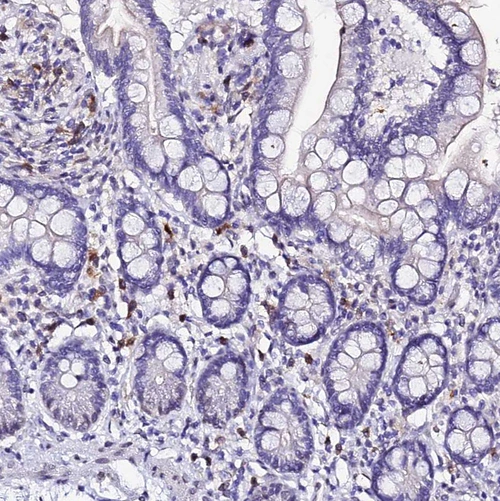

Immunohistochemical staining of human bone marrow shows strong nuclear positivity in hematopoietic cells.